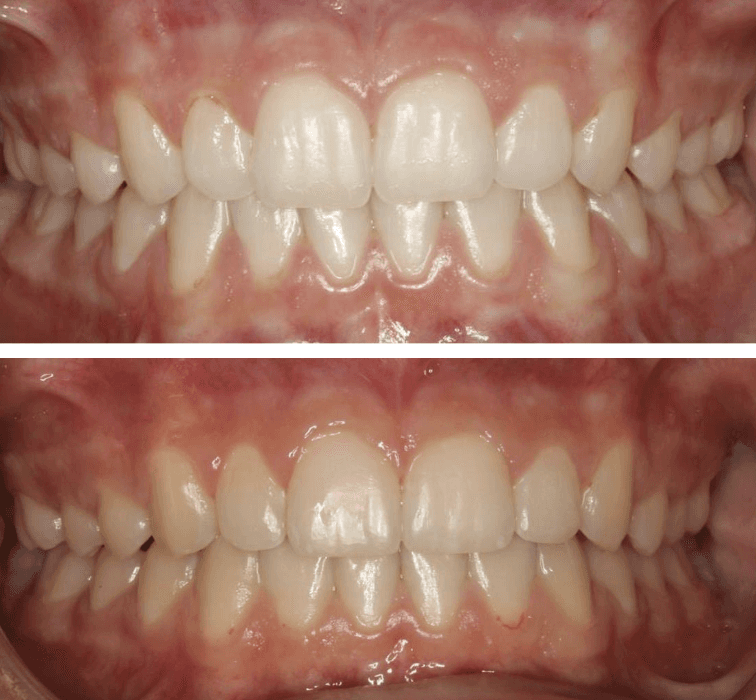

Initial treatment

INTRAORAL